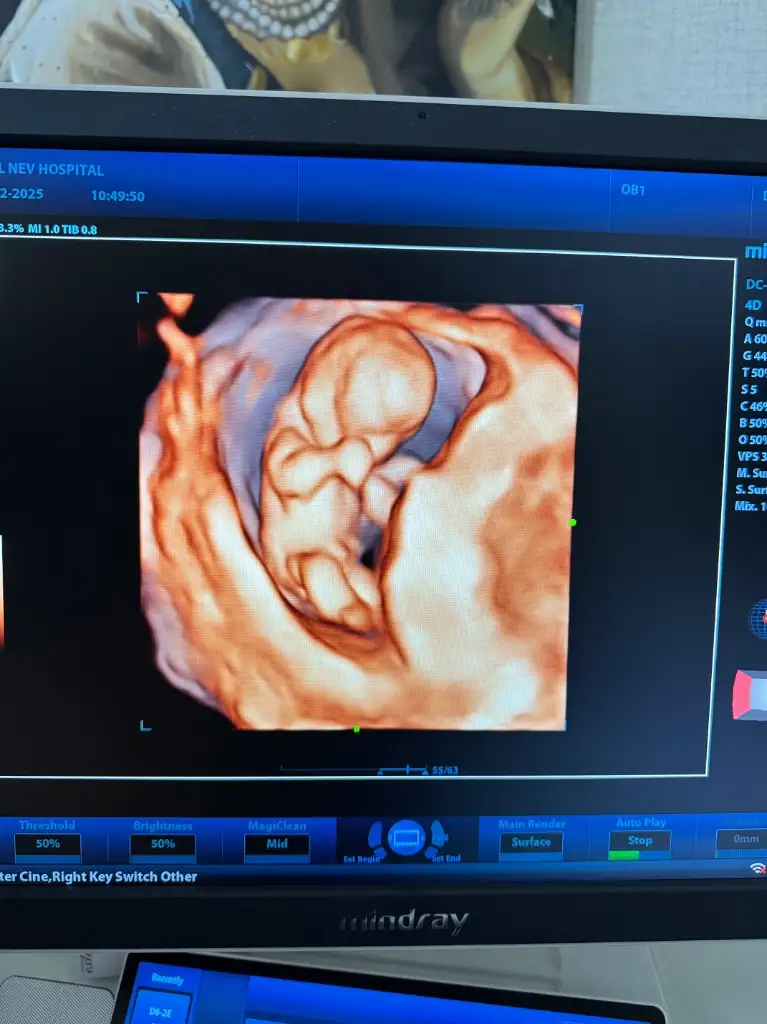

Selam cnm ayy nasılsın maşallah bebiş büyümüş ya cinsiyeti belli oldumu 🥰

Selam tatlım. Çok iyiyim mide bulantılarım oluyor inanılmaz derece de ilaç kullanıyorum. 11+2 haftada %70-80 kıza benziyor demişti. Dün gittik 12+6 tahmin de bile bulunmadı doktorum. Çok üzüldüm. :( sizlerin nasıl gidiyor

İyi bizde işte hala bekliyoruz sabırla kesenin fotosu varmı bakayım bende

En yakın zaman da inşallah güzel haberi alırsın kuzucum. En başından beri kız hissediyorum 🥹 sabırsızlanmaya başladım artık